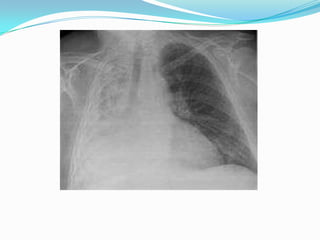

EXAMENESBroncoscopia Radiografía de tórax: Detecta los siguientes signos radiológicos:Desplazamiento de las cisuras.Desplazamiento de mediastinoElevación del hemidiafragma.Aproximación arcos costales.Enfisema compensador.Aumento de la densidad pulmonar sin broncograma.En el adulto previamente sano que presente una atelectasia hay que sospechar una neoplasias que obstruye el bronquio.

EXAMENESBroncoscopia Radiografía detórax: Detecta los siguientes signos radiológicos:Desplazamiento de las cisuras.Desplazamiento de mediastinoElevación del hemidiafragma.Aproximación arcos costales.Enfisema compensador.Aumento de la densidad pulmonar sin broncograma.En el adulto previamente sano que presente una atelectasia hay que sospechar una neoplasias que obstruye el bronquio.